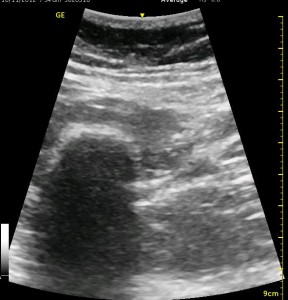

The following ultrasound image shows typical relationships of the sonoanatomy of the anterior sciatic nerve block. The femur is at 4cm on the right (lateral) of the image seen as a bright white horizontal line. Typically, there is a bone shadow below it, though there is some artifact below the femur here. The femoral vessels are seen between the 2cm and 3cm marks just to the right of center as a darkened area. They really can be determined by pausing for the appearance of arterial pulsation and venous compressibility. The adductors are seen to the left of the femur as a darkened area. Just deep to this between the 6cm and 7cm mark is a brightened rectangular shape, the sciatic nerve. The brightness fill fade with rocking of the probe over it. The nerve can be approached from the medial or lateral aspect of the probe, and moving the probe medially will sometimes allow for a better trajectory.

The image above is not an obvious one, and I did that on purpose. You have to get used to the idea that you will not always have a ‘super distinct’ image with this approach, and you will often need to use a number of additional clues to find your target and then to put local around it. I think the only way to really get a handle on being able to identify the basic elements is to look at several images over and over, so I have provided several below for you to use for practice. Note that the sciatic nerve will ‘poke out’ from behind the femur to different degrees depending on your orientation to the femur as well as to how far up or down the femur you go. It will be seen more if you are proximal. See how well you can identify the structures in the images below.